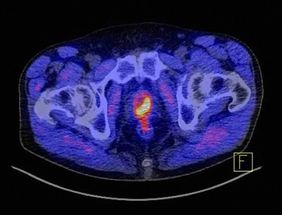

Der 4. Patienteninformationstag des Prostatakarzinomzentrums des Uniklinikums Würzburg am 18. April 2020 beschäftigt sich mit der Diagnostik, Therapie und komplementären Aspekten. Die Abbildung zeigt, wie markant ein Prostatakarzinom unter Zuhilfenahme des Tracers PSMA im PET-CT als gelb-rotes Objekt dargestellt wird. Bild: Uniklinikum Würzburg